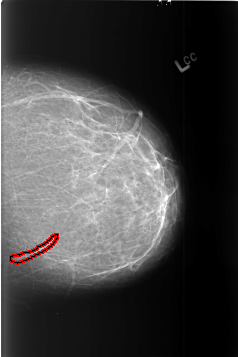

FILE: B_3453_1.LEFT_MLO.OVERLAY

TOTAL_ABNORMALITIES 1

ABNORMALITY 1

LESION_TYPE MASS SHAPE TUBULAR MARGINS N/A

ASSESSMENT 2

SUBTLETY 3

PATHOLOGY BENIGN_WITHOUT_CALLBACK

TOTAL_OUTLINES 1

BOUNDARY